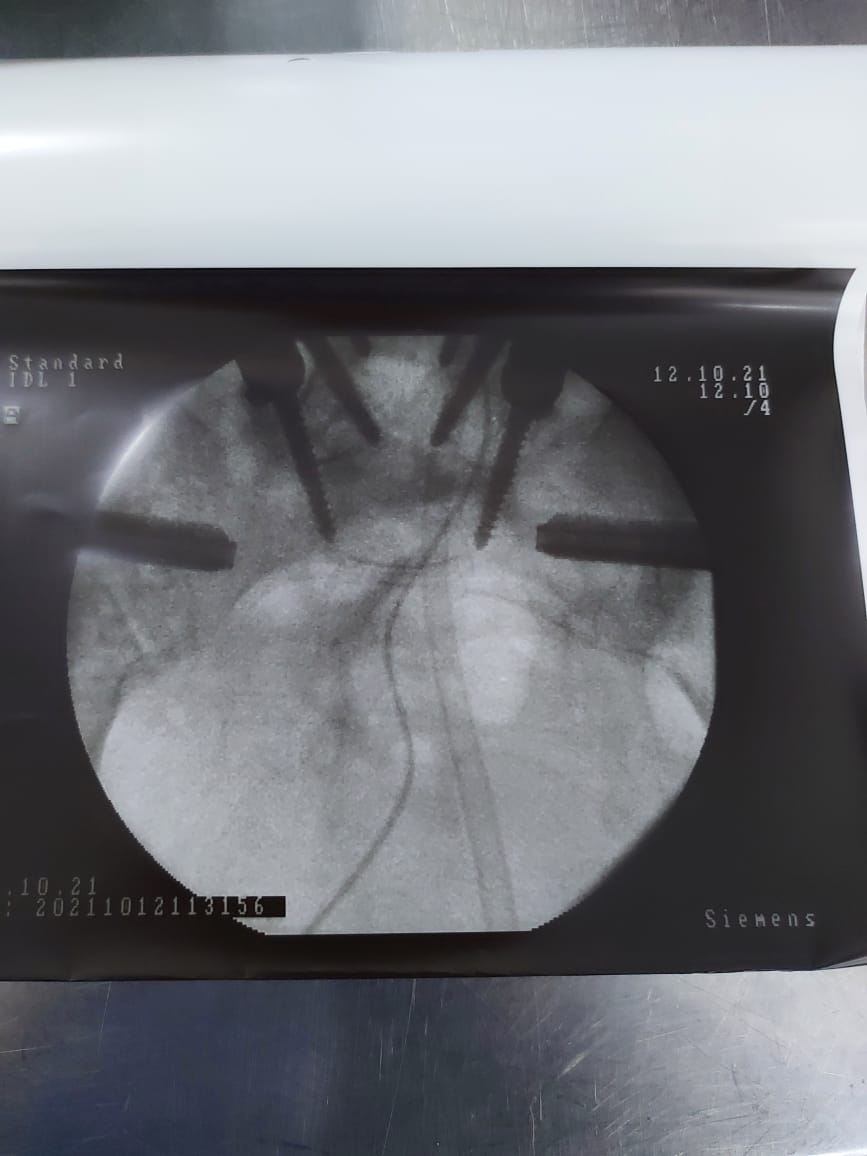

وقال الدكتور حازم مقابلة لـ "مدار الساعة " أن المريضة كانت تعاني من تنكسات شديده في مفاصل الحوض المتصله بأسفل العمود الفقري نتيجة اصابتها السابقة بمرض الروماتيزم مما اثر على حياتها العمليه واليوميه، حيث جرى تثبيت مفاصل sacroiliac joints بواسطة تقنية جديدة وهي H.A coated titanium bars.

واستغرقت العملية نحو نصف ساعة لتتمكن المريضة من السير على قدميها مجدداً بصورة طبيعية في اليوم الثاني من إجراء العملية.